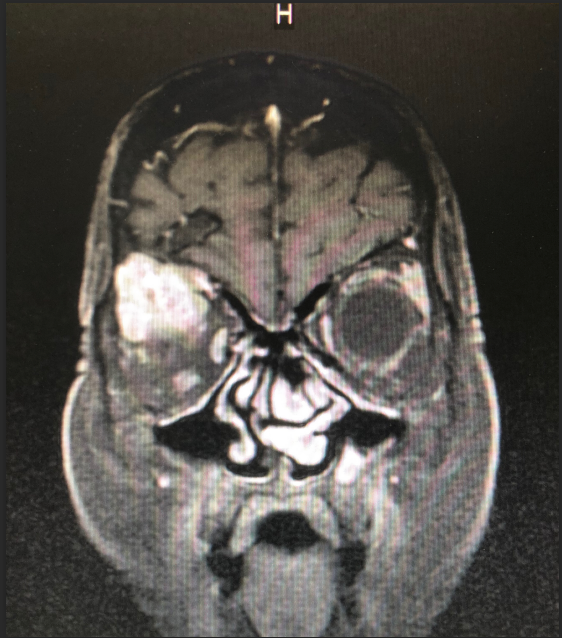

患者王女士,79岁,女性,2周前出现右眼疼痛,眼球突出,随后眼痛逐步加重,右眼视力急剧下降。在当地成人导航 被诊断为眼眶内肿瘤,需手术治疗。但因患者眼眶肿瘤突破眼眶,向颅内生长,手术难度大。患者先后辗转多家成人导航 眼科均无功而返。患者右眼疼痛难忍,最终选择到成人导航 寻求最后的帮助。

成人导航 神经外科团队接诊后对患者进行了全面检查,诊断为右眼眶肿瘤。因患者肿瘤向颅内生长,颅底及眼眶骨质已完全破坏,传统的手术方式不仅创伤大,更可能因为颅底结构无法完全重建导致患者脑脊液漏,引起颅内感染。神经外科联合眼科进行了手术方式的讨论,根据术中可能出现的各种情况其制定了详细的治疗方案,认真完善术前准备后,于2018年12月24日成功为其开展“完整切除颅内外沟通瘤并颅底眼眶重建修复手术”,手术过程非常顺利,术后患者无视神经损伤,视力较术前明显改善。目前患者已康复出院。